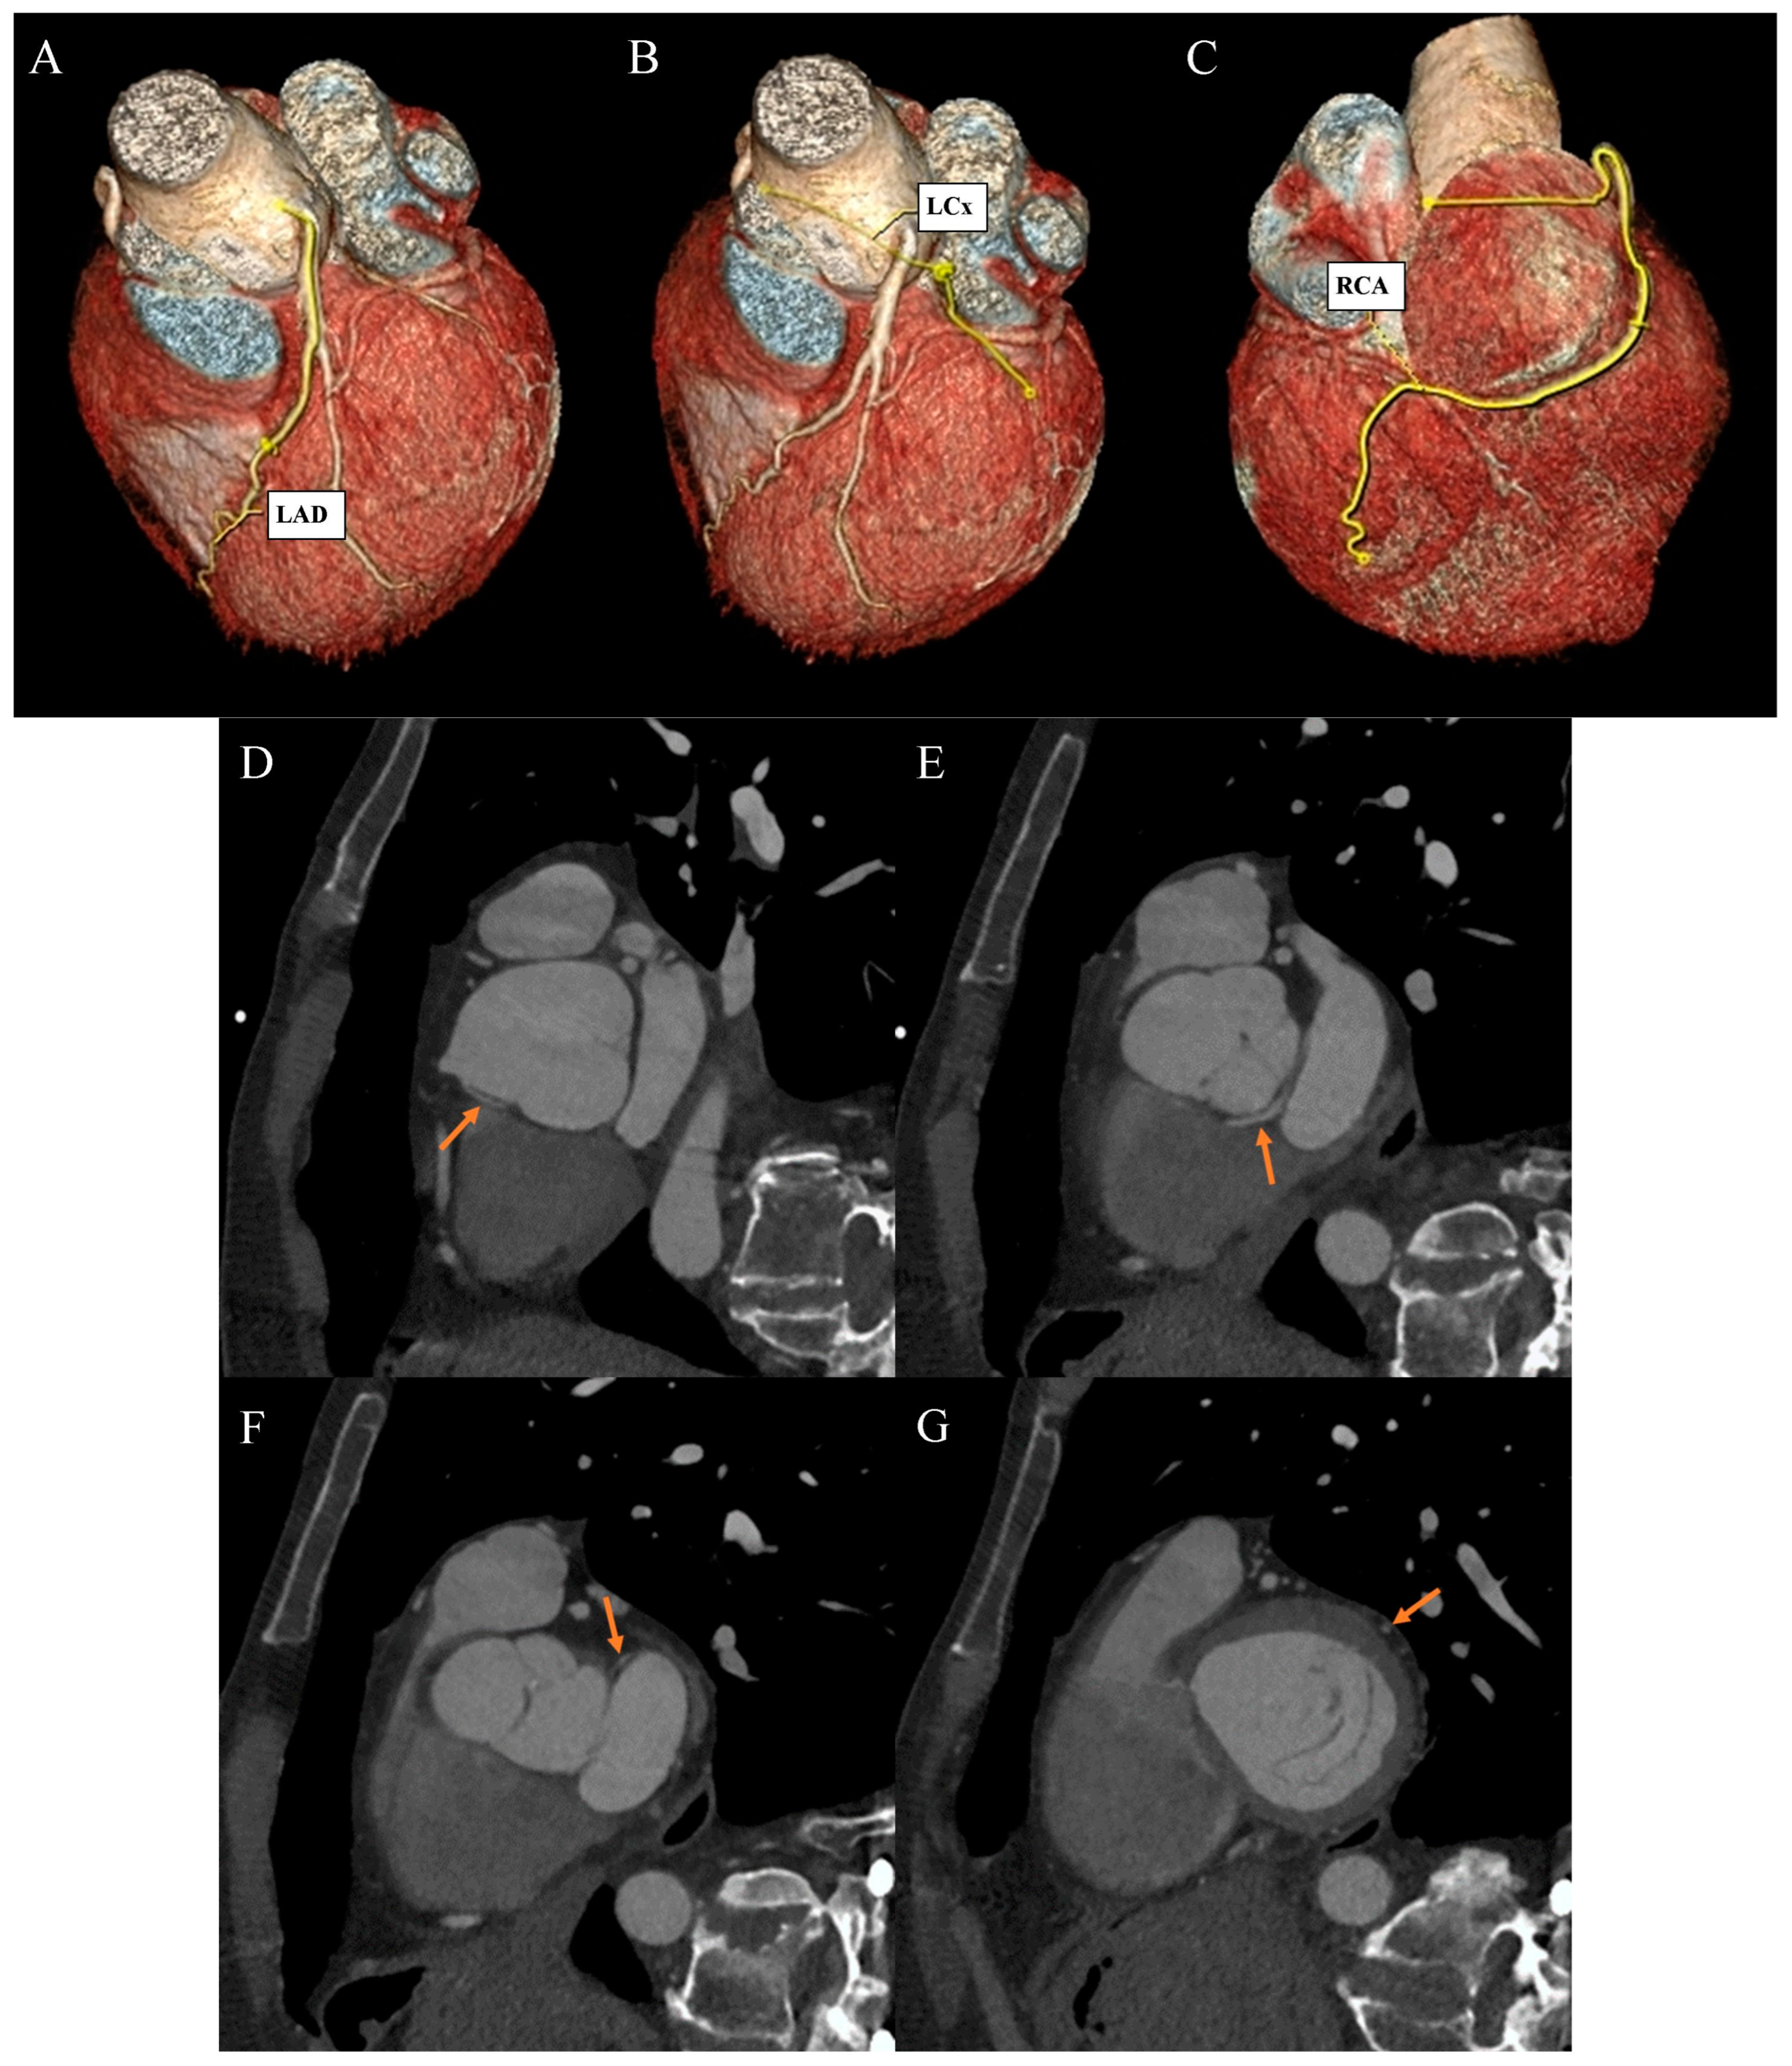

Figure 2.

Coronary artery computed tomography angiography. Coronary artery anomaly. (A) Volume-rendering technique reconstruction. Left anterior descending (LAD) artery with a direct origin from the left aortic bulb sinus. (B) Volume-rendering technique reconstruction. Distal left circumflex artery (LCx) segment as a continuation of the branch located between the aortic bulb and left atrium wall. (C) Volume-rendering technique reconstruction. Dominant right coronary artery (RCA) with a typical course. (D) Multiplanar reconstruction. Oblique view. The arrow indicates the ectopic origin of LCx from the right aortic bulb sinus. (E) Multiplanar reconstruction. Oblique view. The arrow indicates the retroaortic course of the proximal LCx segment. (F) Multiplanar reconstruction. Oblique view. The arrow indicates the course of the medial LCx segment between the aortic bulb and left atrium. (G) Multiplanar reconstruction. Oblique view. The arrow indicates a typical course of the distal LCx segment.